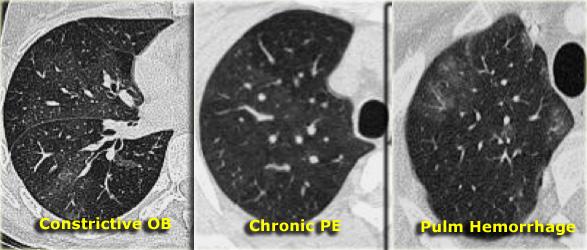

Mosaic attenuation

Thuật ngữ suy giảm khảm mô tả sự khác biệt về tỷ trọng giữa các vùng phổi bị tổn thương và không bị tổn thương, tạo ra hình ảnh loang lổ xen kẽ giữa các vùng phổi sáng và tối. Vai trò của bác sĩ X-quang là xác định thành phần nào — vùng phổi tối hay vùng phổi sáng — là bất thường.

Việc phân biệt các thực thể này có thể là một thách thức. Hai dấu hiệu chẩn đoán giúp phân biệt thêm:

- Expiratory scans for air trapping.

- Đánh giá mạch máu:

- Nếu mạch máu kém rõ hơn ở vùng phổi “đen” so với phổi “trắng”, thì vùng phổi “đen” có khả năng là bất thường. Điều này gợi ý viêm tiểu phế quản tắc nghẽn hoặc thuyên tắc phổi mạn tính. Chụp cắt lớp thì thở ra có thể giúp phân biệt các tình trạng này.

- Nếu mạch máu xuất hiện tương tự nhau ở cả vùng phổi “đen” và “trắng”, bệnh nhân có khả năng mắc bệnh phổi thâm nhiễm, chẳng hạn như xuất huyết phổi (như được minh họa ở bên phải).

Suy Giảm Thông Khí Dạng Khảm trong Bệnh Huyết Khối Tắc Mạch Mãn Tính

Hình ảnh bên trái mô tả một bệnh nhân có dạng kính mờ phân bố theo kiểu khảm.

Dấu hiệu chính ở đây là sự giãn rộng của các động mạch phổi (mũi tên) tại các vùng có độ mờ dạng kính mờ.

Hình ảnh này là kết quả của vùng phổi được tưới máu quá mức nằm kề cạnh vùng phổi thiểu máu với khẩu kính mạch máu giảm do bệnh huyết khối tắc mạch mãn tính.

Một bệnh nhân khác (bên trái) cho thấy hình ảnh kính mờ tương tự theo phân bố khảm.

Hình ảnh kính mờ là do vùng phổi được tưới máu nhiều với các mạch máu lớn liền kề với vùng phổi thiểu huyết (mũi tên vàng) với các mạch máu nhỏ do bệnh huyết khối tắc mạch mạn tính.

Huyết khối thành mạch và vách ngăn nội mạch là những đặc điểm điển hình của huyết khối tắc mạch mạn tính, phản ánh sự tái thông một phần (mũi tên xanh).